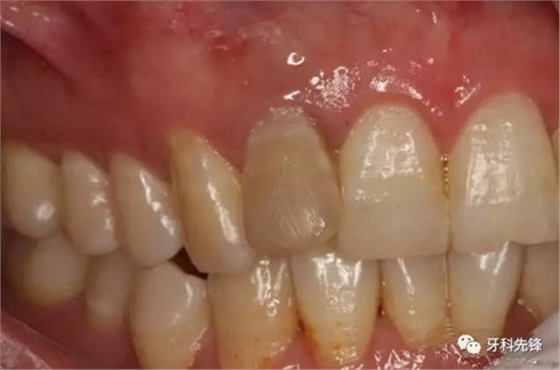

圖2.12牙冠成灰褐色,唇側(cè)粘膜正常。

圖3。12的腭側(cè)未檢查有齲壞及畸形舌側(cè)窩,證明12牙根未發(fā)育完成是含牙囊腫影響所致。